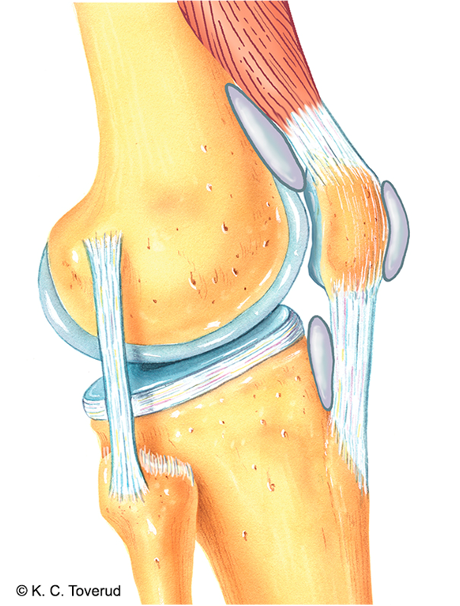

Patella palpasjon samtidig som knebøy. Krepitasjon. Smerte.

Smerter fra

- Oppflosset leddbrusk i femuropatellarleddet

- Bursa prepatellaris, suprapatellaris, infrapatellaris

- Quadricepssene

- Patellarsene

Se og palper etter hevelse (husk å palper i fossa poplitea etter Bakercyste), rubor og varme.

Sjekk patella dip, positiv test dersom > 20ml som tyder på intraartikulær væske.

Varme

Patella dip test, positiv når > 20 mø intraartikulær væske

Fokusområde: Systematisk kartlegging av strukturer for å bekrefte tentative diagnoser.

- Quadricepssenen → tendinopati/ruptur

- Patella → prepatellær bursitt

- Varme → artritt, bursitt

- Patella dip test → intraartikulær væske (positiv test når >20 ml intraartikulær væske)